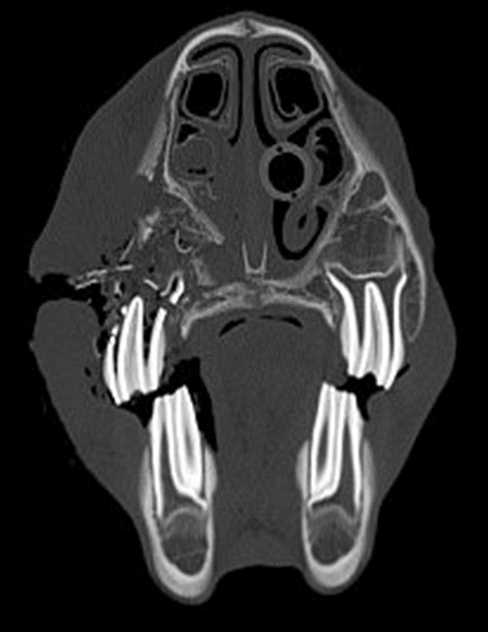

Diagnostic imaging identified the fractures to be complete and comminuted in all cases. The skull fractures were unilateral in 10 horses and bilateral in 3 cases. The most common facial bones involved were the maxilla in 9 horses, the nasal bone in 7 horses, and the frontal bone in 4 horses. The nasolacrimal duct was involved in 3 horses and the infraorbital canal in 1 horse. Secondary sinusitis was present in 10 horses with the rostral maxillary, caudal maxillary sinus, and ventral conchal sinus being the most affected. There was an associated fracture of dental structures in 3 horses (Figure 2a and Figure 2b).

Treatment was strictly conservative in half of the cases, consisting of wound treatment and systemic antibiotics and anti-inflammatories, as needed. In the other half of the cases, some minimal surgical intervention was undertaken and included removal of loose bony fragments and sinus trephine and sinoscopy, fragment removal and sinus flush through a Foley catheter and dental extraction. In most cases, the lacerations were cleaned, debrided, and closed primarily using either simple interrupted or tension-relieving sutures (vertical mattress). In certain cases, given the nature of the laceration, only partial closure was possible leaving a defect to heal by second intention. (Figure 2a)